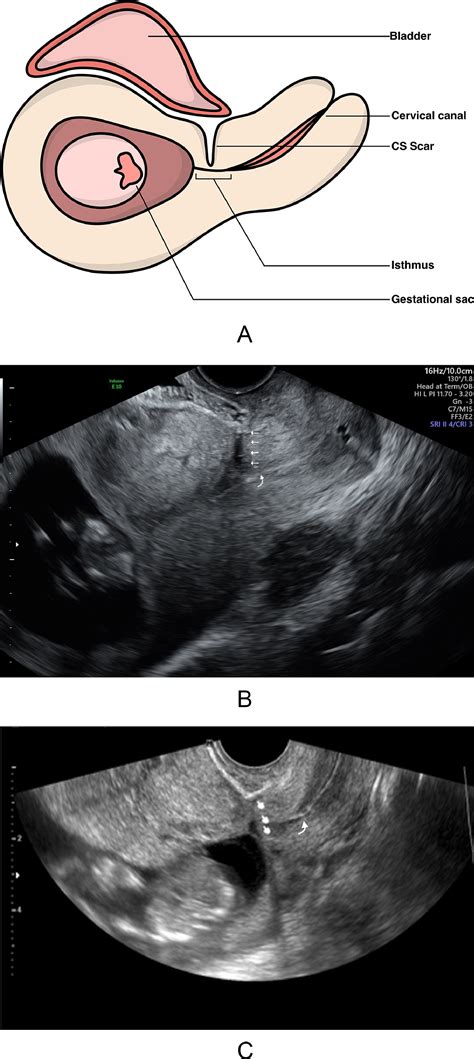

Modern obstetric imaging has made the identification of Placenta Accreta Spectrum much more reliable than in the past. Most cases are identified during the second or third-trimester ultrasound, where specific markers of abnormal placental vascularity are sought by trained sonographers.

Diagnostic Marker Description

Loss of Retroplacental Clear Zone The thin, hypoechoic area between the placenta and the uterus disappears.

Abnormal Placental Lacunae Large, irregular vascular spaces within the placenta that may resemble "Swiss cheese."

Bladder Wall Interruption The interface between the bladder and the uterus appears irregular, suggesting deep invasion.

Exophytic Mass Placental tissue bulging beyond the normal uterine contour.

⚠️ Note: While ultrasounds are highly effective, MRI is often utilized as an adjunct imaging tool to provide better visualization of the depth of invasion, especially in cases where the placenta is located on the posterior wall of the uterus.